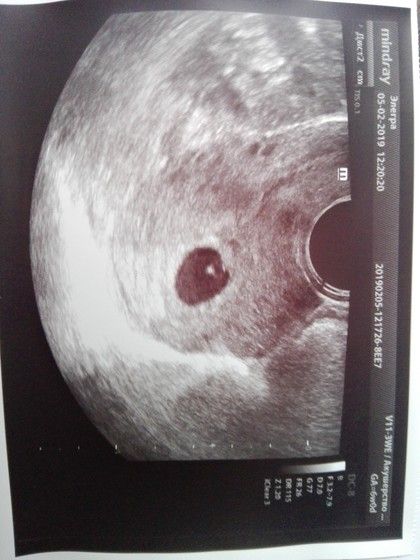

Девочки, пришла на Узи. Все посмотрели, что то врач про себя бормотала и иногда, все нормально. Я попросила фото эмбриона. Спросила какая неделя — Конец шестой (это мой подсчет). Последние месячные 25 декабря!!!

А в заключении у нее стоит 5 недель и 5 дней. Это эмбриональный или акушерский срок? Гинеколог вообще сказала сердечко должно уже биться. Но ничего нигде не указано. Я очень переживаю. Подскажите почему такой срок и нет биения сердца.

Эмбрион есть, на фото видно, она мне его показывала длину на мониторе